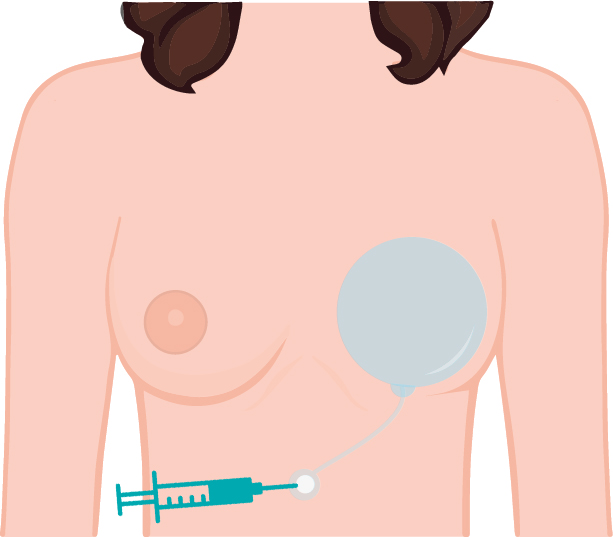

คนที่เป็นมะเร็งเราจะใส่ EXPANDER เพื่อที่จะไปขยายเนื้อเต้านม ที่ถูกฉายแสงและถูกตัดออกไป จะเป็นพังผืดรัดแน่น

ตัวขยายนี้ค่อยๆใส่ลงไป จะมีสายที่ไว้ใช้เติมน้ำเกลือ แพทย์จะนัดผู้ป่วยเพื่อการฉีดขยาย EXPANDER ตัวปุ่มใช้สำหรับฉีดเติมน้ำเกลือผ่านสายที่ติดกับแผ่นจะใช้ฝังไว้ที่ใต้หน้าอกช่วงกลางๆ และมาร์คจุดไว้

และค่อยๆเพิ่มน้ำเกลือตามระยะเวลา ค่อยๆขยายไปเรื่อยๆ ขยายจนเท่ากับขนาดที่เราต้องการ

ประมาณ 2-3 เดือนค่อยเอาออก แล้วค่อยใส่ Silicone เข้าไปแทน

คนที่เป็นมะเร็งเราจะใส่ EXPANDER เพื่อที่จะไปขยายเนื้อเต้านม ที่ถูกฉายแสงและถูกตัดออกไป จะเป็นพังผืดรัดแน่น

ตัวขยายนี้ค่อยๆใส่ลงไป จะมีสายที่ไว้ใช้เติมน้ำเกลือ แพทย์จะนัดผู้ป่วยเพื่อการฉีดขยาย EXPANDER ตัวปุ่มใช้สำหรับฉีดเติมน้ำเกลือผ่านสายที่ติดกับแผ่นจะใช้ฝังไว้ที่ใต้หน้าอกช่วงกลางๆ และมาร์คจุดไว้

และค่อยๆเพิ่มน้ำเกลือตามระยะเวลา ค่อยๆขยายไปเรื่อยๆ ขยายจนเท่ากับขนาดที่เราต้องการ

ประมาณ 2-3 เดือนค่อยเอาออก แล้วค่อยใส่ Silicone เข้าไปแทน